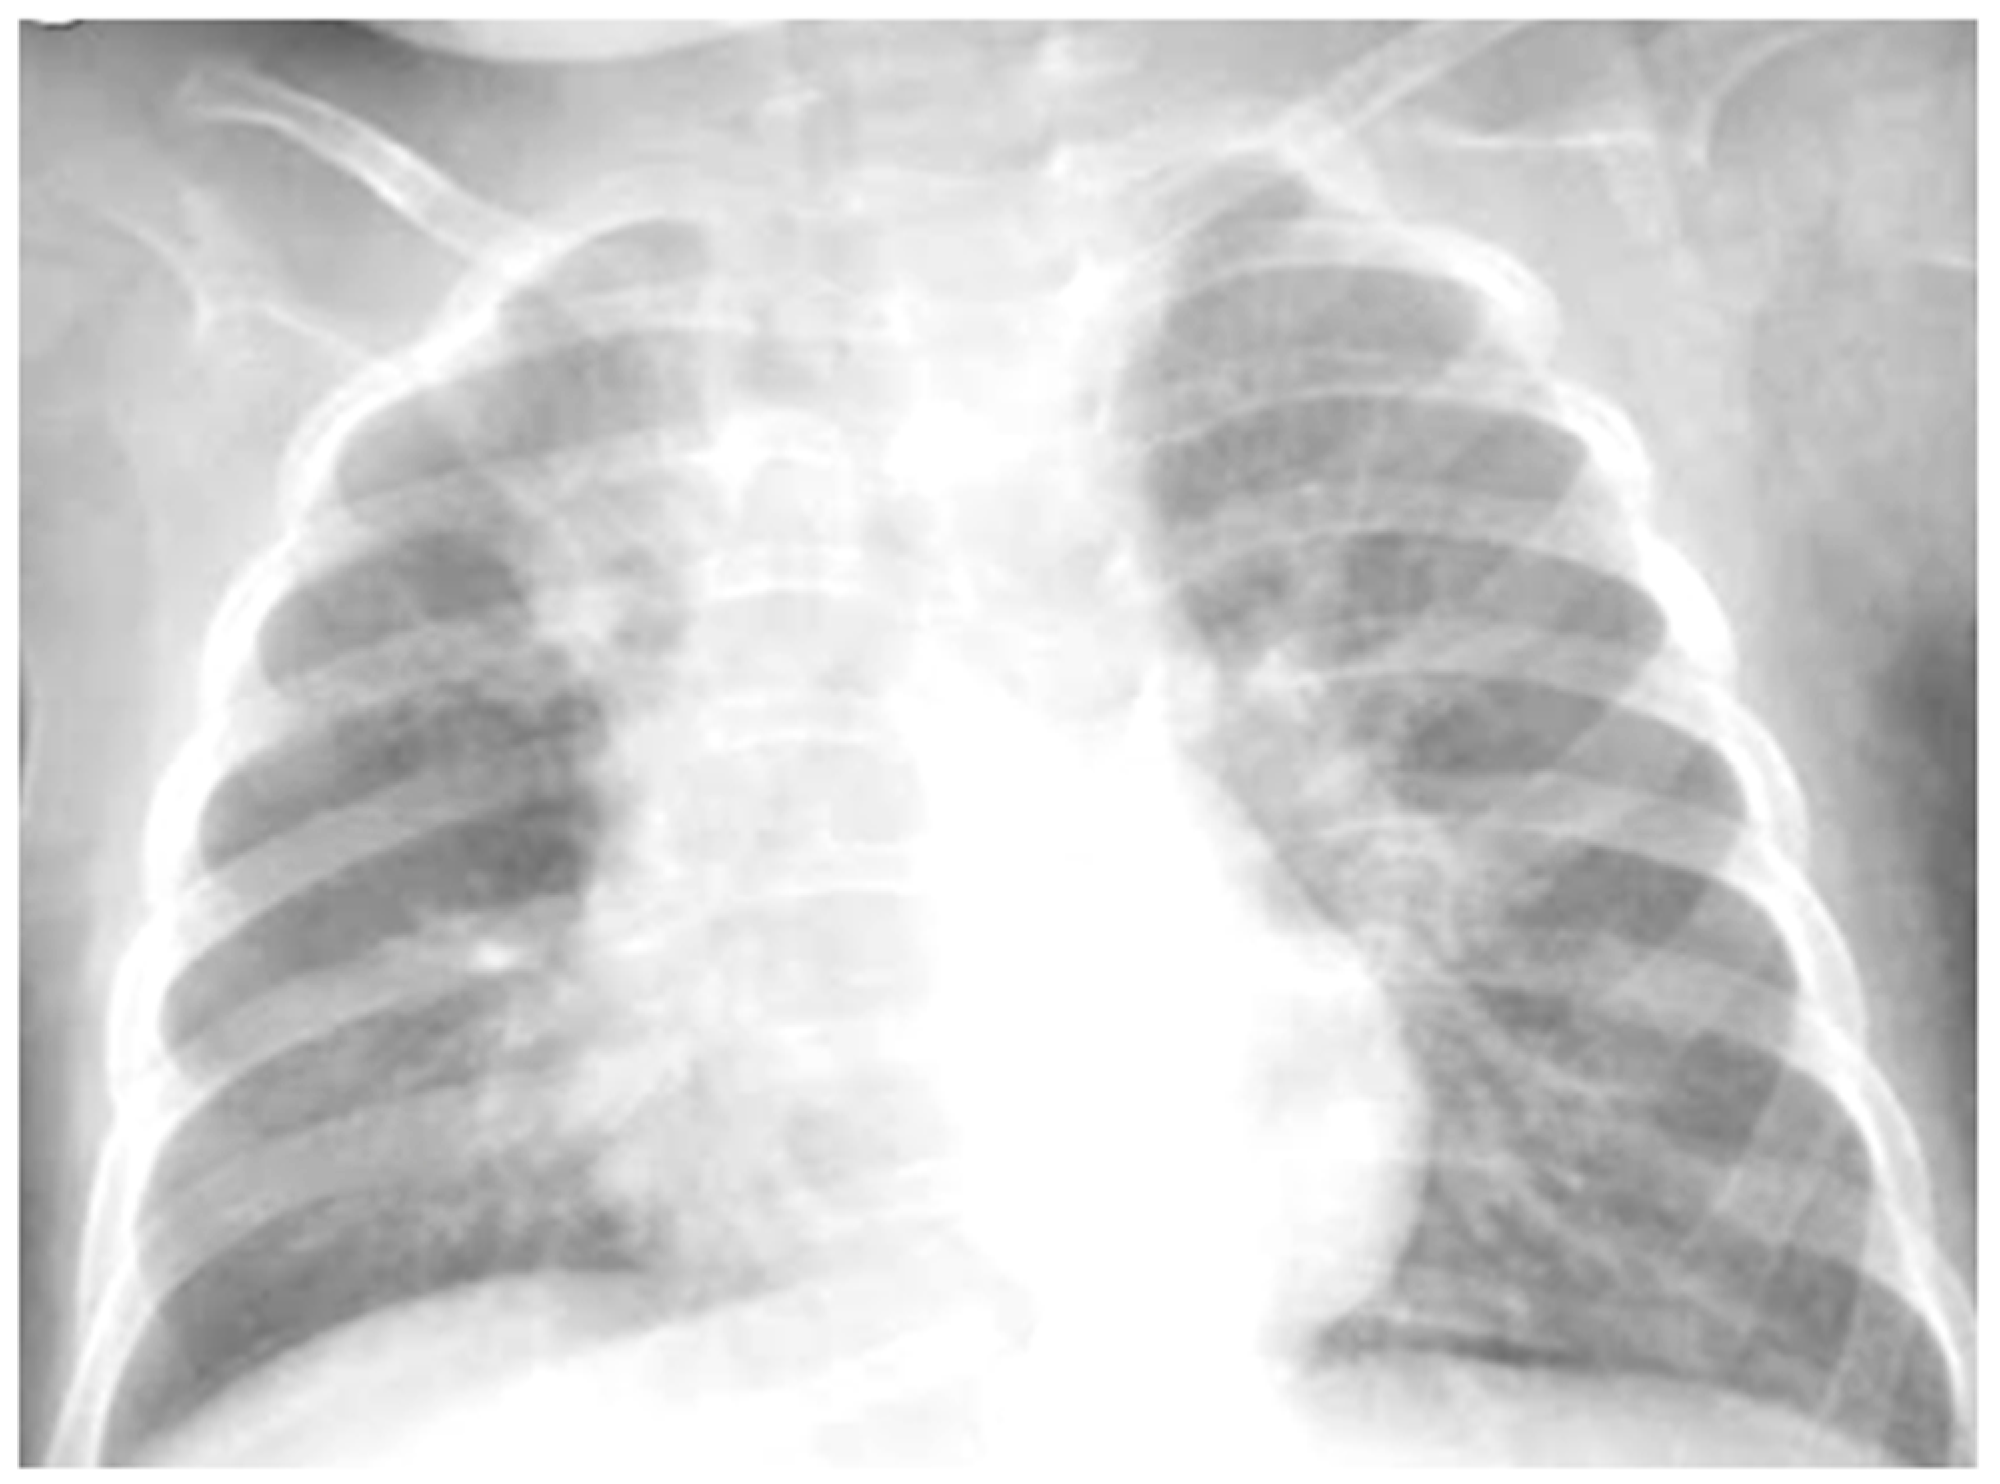

He came to our attention at the PED for acute onset of severe respiratory distress with diffuse bronchospasms and moderate-to-severe acute asthmatic attack: he presented severely dyspneic and tachypneic, unable to speak, he was tachycardic, and he had an oxygen saturation of 88–90% with consequent oxygen requirement. A chest X-ray was performed in the pediatric emergency room to rule out respiratory complications in consideration of the severity of the severe clinical picture. The radiographic picture (Figure 2) was interpreted as an inflammatory type consolidation. However, the child was apyretic, and the inflammation indices were negative, as were the molecular and culture microbiological tests of the airways for both viruses and bacteria.

Chest radiography shows, on the left inferior lobe, non-specific areas of reduced transparency, associated with obliteration of the left lateral costophrenic sinus. It shows further subtle parenchymal hypodiaphania on the right mid-basal area.